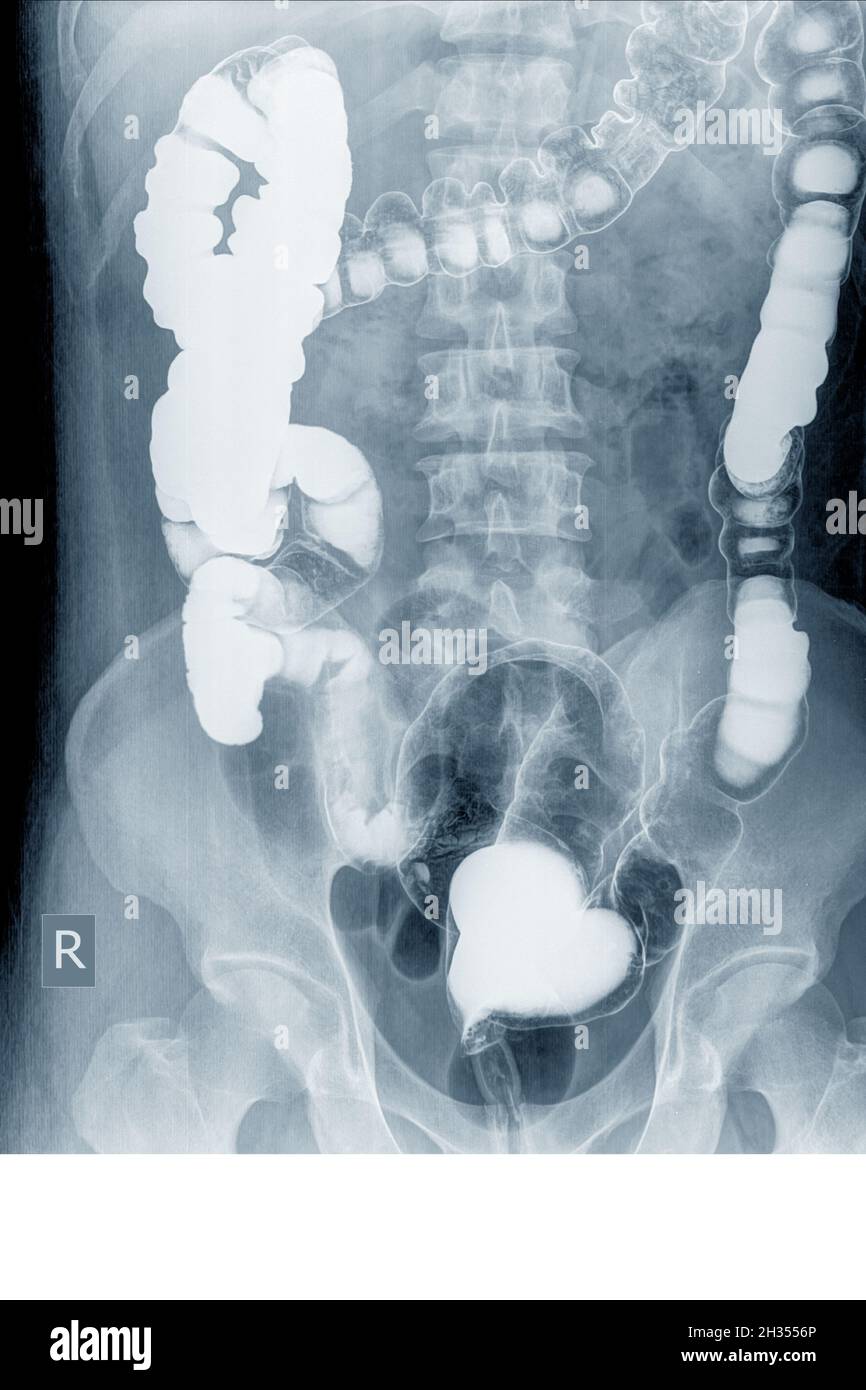

From www.alamyimages.fr

Barium enema x ray Banque de photographies et d’images à haute Beaucoup D'air Dans Le Colon L’aérocolie désigne une accumulation de gaz dans le côlon. Quelle est la définition de l'aérocolie ? L'aérocolie est liée à une surproduction de gaz et leur présence en excès à l'intérieur. Nous parlons plus communément de ballonnements. Les troubles digestifs, certains troubles digestifs, tels que le syndrome du côlon irritable (sci) ou la maladie inflammatoire de l'intestin (mii), peuvent entraîner. Beaucoup D'air Dans Le Colon.

From www.researchgate.net

Abdominal Xray. The colon is filled with air from the ascending colon Beaucoup D'air Dans Le Colon L’aérocolie désigne une accumulation de gaz dans le côlon. L’aérocolie est un trouble digestif commun, la plupart du temps bénin, qui correspond à une accumulation de gaz dans le côlon. Quelle est la définition de l'aérocolie ? Avaler deux à quatre litres d’air par jour est tout à fait normal. Nous parlons plus communément de ballonnements. Mais un trop gros. Beaucoup D'air Dans Le Colon.